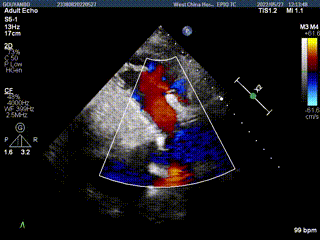

团队前期经过多次讨论,制定了周密的手术策略和预案。由于患者已是近九旬的超高龄老人,传统外科开胸手术风险极高,纯介入经血管三尖瓣替换能够明显减少创伤。术中陈茂及冯沅教授结合体表定位在造影指示下精准穿刺右侧颈静脉并预置两把血管缝合器。成功建立经皮血管入路后在食道超声和DSA的引导下顺利完成人工瓣膜植入,术后超声和造影显示人工三尖瓣同轴性良好,瓣架固定牢靠,无反流和瓣周漏,平均跨瓣压差降为1mmHg。术毕收紧预置的血管缝合器缝线完成止血,缝合效果满意,在手术室即刻拔除气管插管。

术后超声